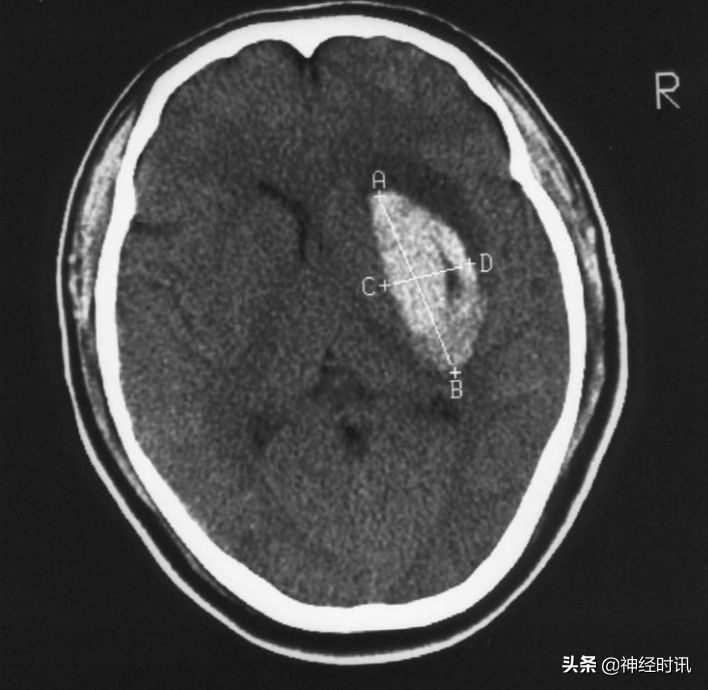

① 急性期CT显示高密度影。

② 可显示出血部位,出血量,中线移位,有否破入蛛网膜下腔及脑室,有助于指导治疗和判断预后。

③ 血肿量计算法,血肿量=长×宽×层面×π/6